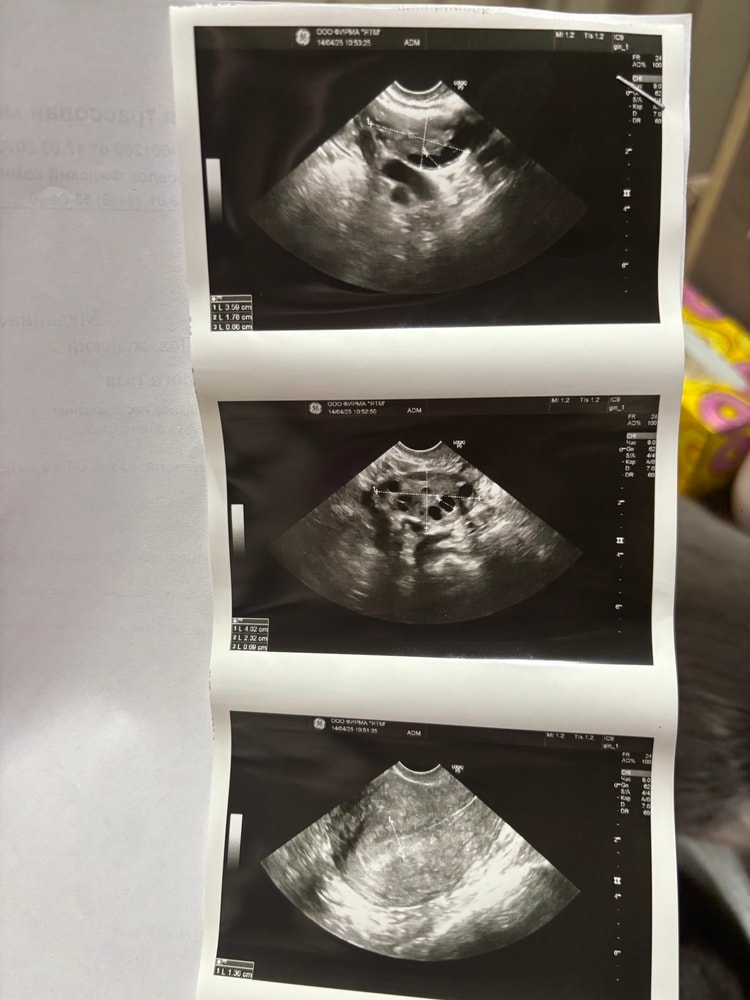

Ох не знаю с чего начать… в феврале было крио на згт, неудача. Сделала в марте гистеро выявили полип и хэ, удалили вакуумом хэ пролечила. Сейчас готовлюсь ко второму переносу на 22 апреля, очень сильно смущает эндометрий, назначили большую дозу эстрогена в итоге уже пышный 13.6 это ладно тут еще неоднородность присутствует 😩 На онлайн приеме репродуктолог сказала что ее больше смущает неоднородность но раз я пролечила хэ будем делать перенос. Остались считаные дни сижу и ломаю голову стоит ли ехать с таким эндометрием? Мне кажется тут два исхода либо меня пошлют домой и отменят перенос либо перенесут но закончится все снова неудачей 😩 девочки кто разбирается в узи? На сколько все плачевно ? Фото репродутологу забыла отправить 🤦🏼♀️ Может у кого то был похожий случай и делали перенос с неоднородным эндометрием ?